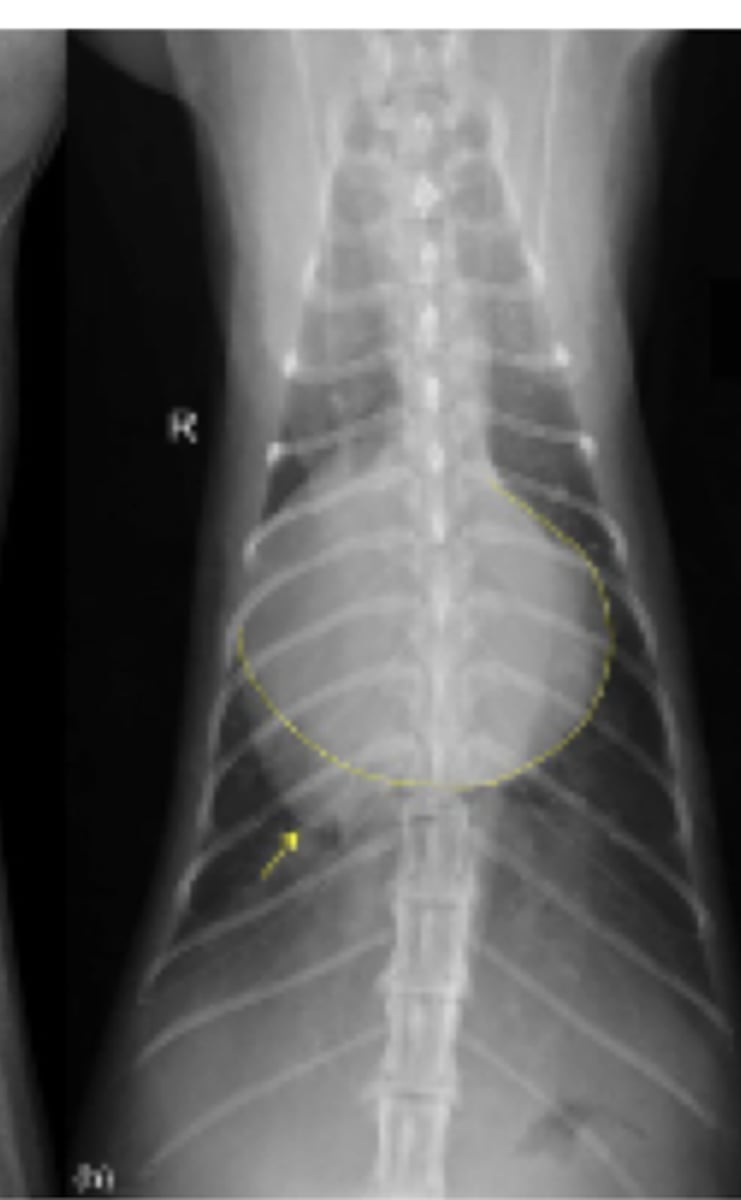

efusión abdominal

patología: